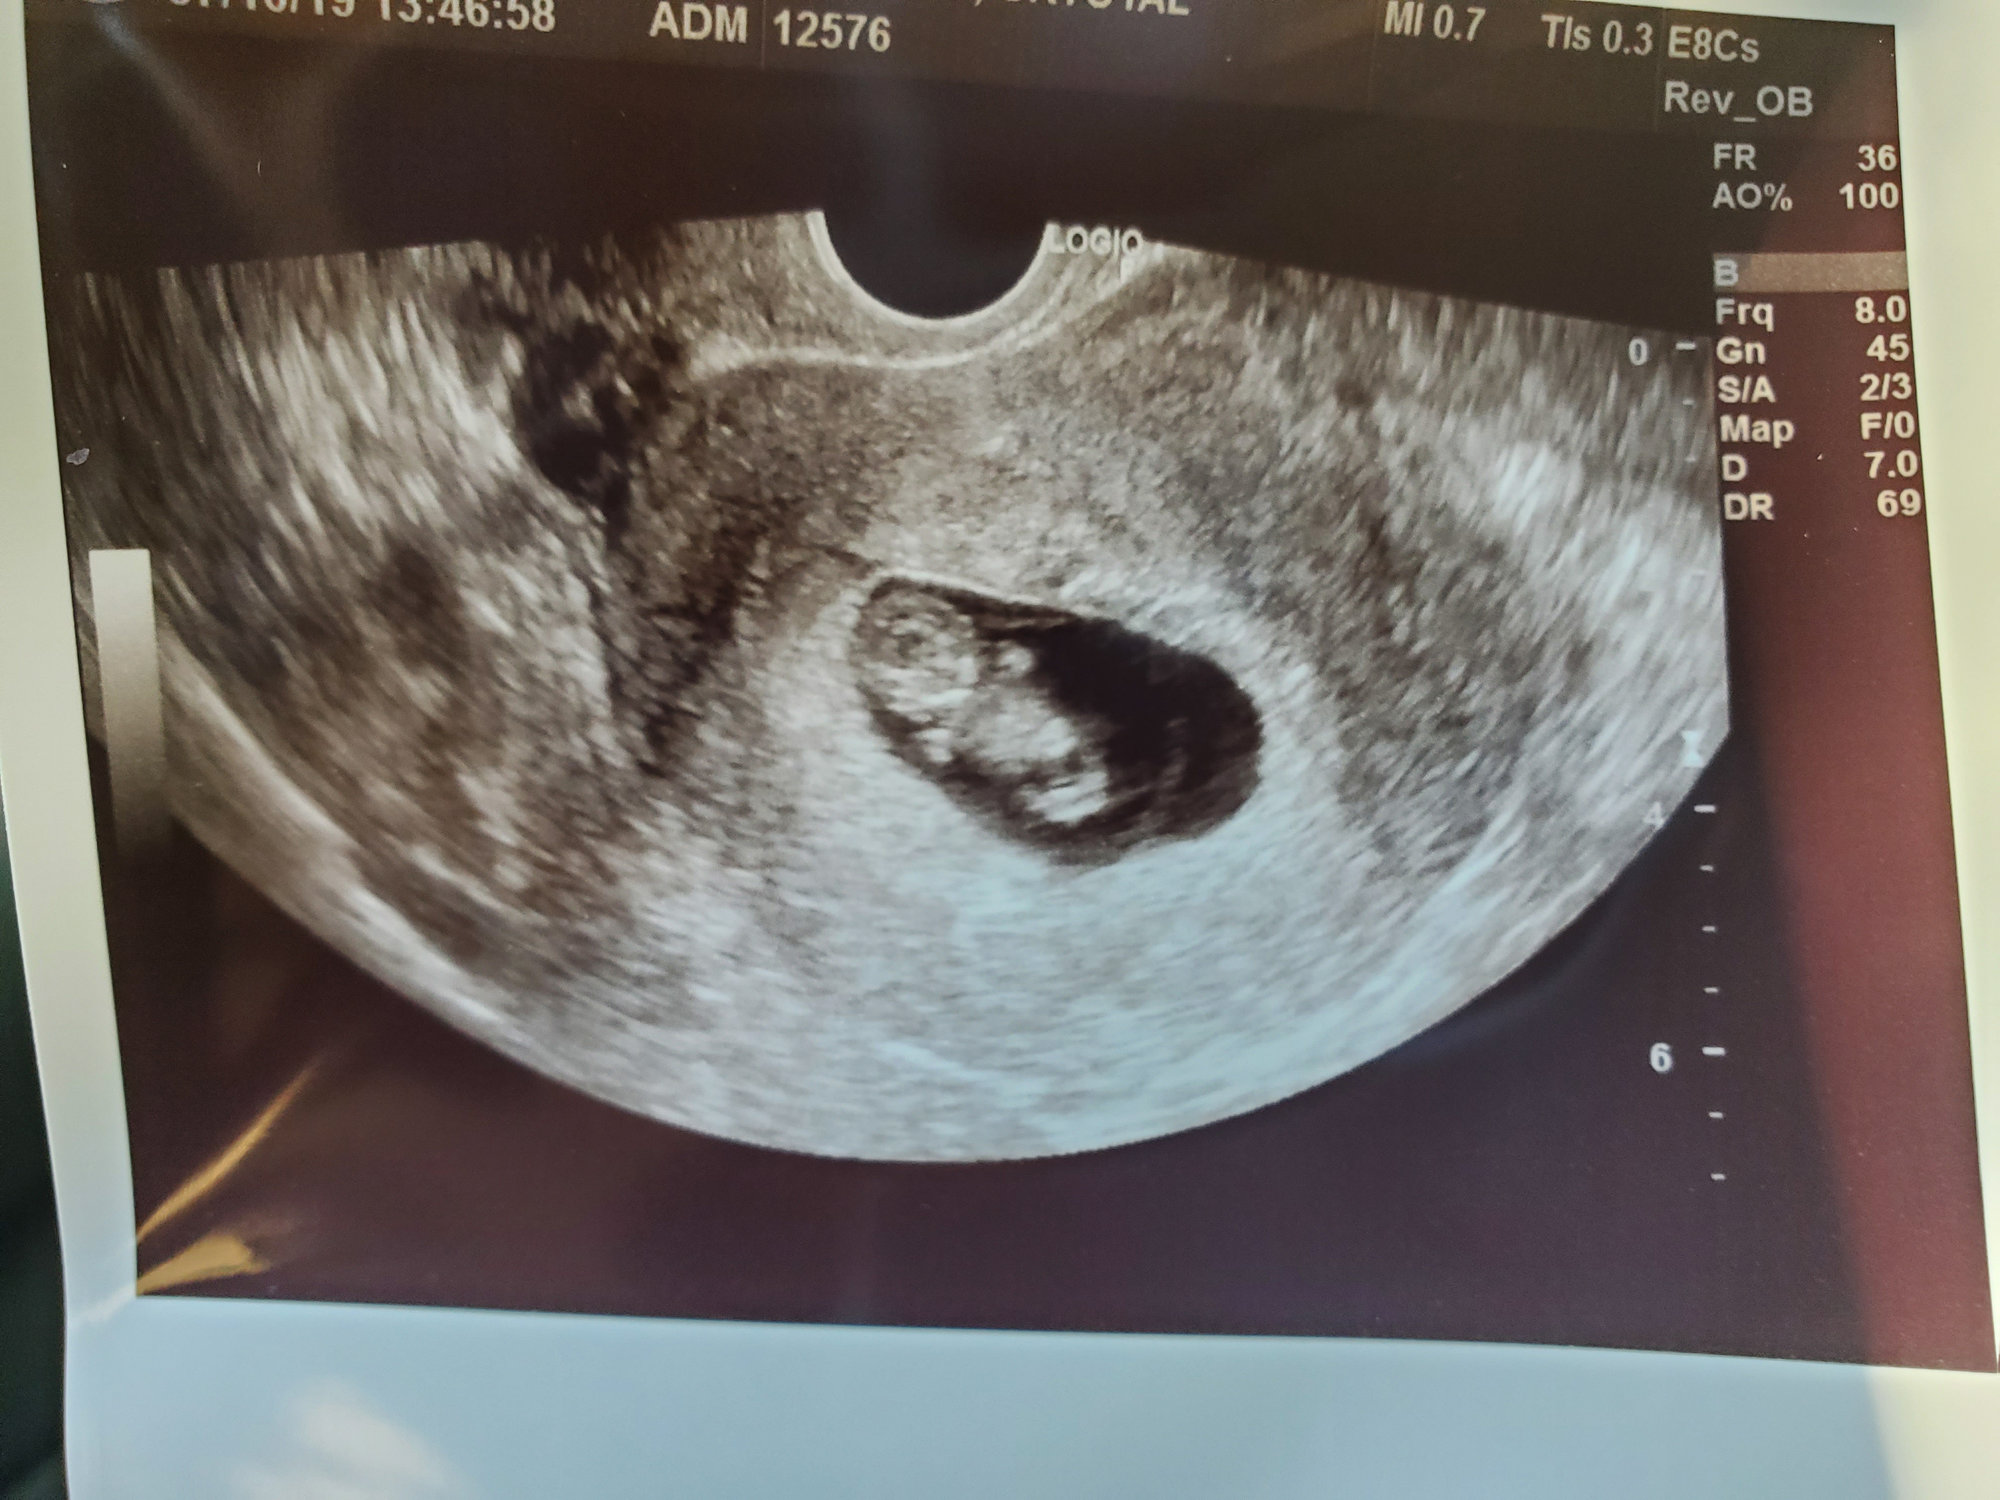

I had my first OB appointment today and got my first picture of my “bat” baby. I call him/her my bat baby because s/he is chillin’ upside down 🤪 HR was strong at 171. I just love this little bat baby already 🥰